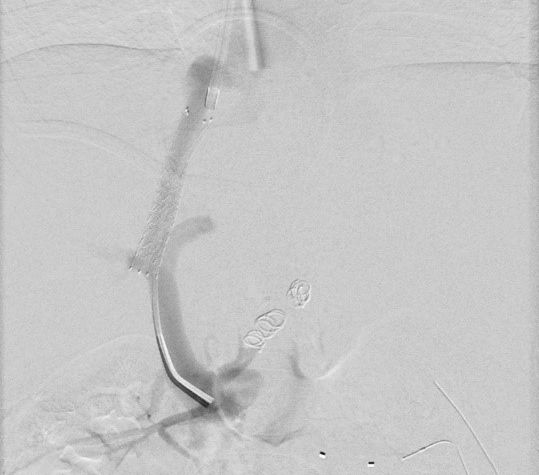

3- jähriger Junge mit stattgehabter Pfortaderthrombose (Verschluss der Pfortader).

Zustand nach Anlage eines Meso-Rex Shunts. Aktuell Größenzunahme der Milz und zunehmende Zeichen des Pfortaderhochdrucks. Sonographisch wurde dann der Verdacht auf eine Stenose (Verengung) der Shunts gestellt. In der Angiographie mit einem Zugang über Milz zeigte sich die vermutete Stenose (Pfeil in Bild A). Es wurde dann ein Stent eingebracht und mittels Ballon dilatiert (B). In der Kontrolle zeigte sich ein gutes Ergebnis mit Beseitigung der Engstelle. Dem Patienten ging es rasch besser.